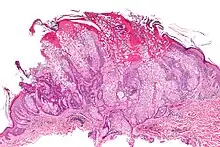

Micrograph of a sebaceous adenoma, as may be seen in Muir–Torre syndrome. H&E stain.

Muir–Torre syndrome is a rare hereditary, autosomal dominant cancer syndrome[1]:663 that is thought to be a subtype of HNPCC (Lynch syndrome). Individuals are prone to develop cancers of the colon, genitourinary tract, and skin lesions, such as keratoacanthomas and sebaceous tumors. The genes affected are MLH1,[2] MSH2,[3] and more recently, MSH6,[4] and are involved in DNA mismatch repair.